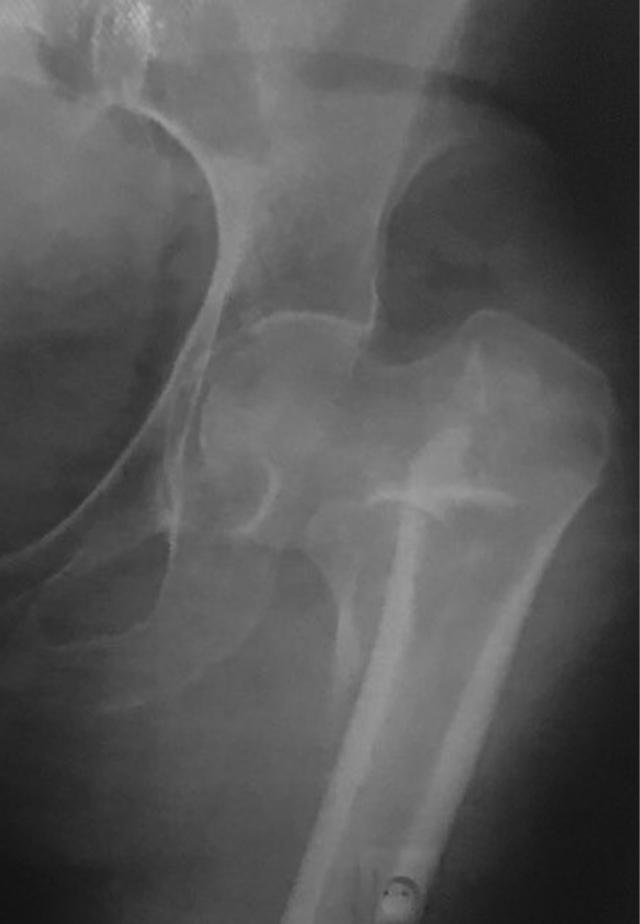

We report a case with implant failure after nailing of an unstable pertrochanteric fracture with dynamic hip screw. The patient presented with a medial sided thigh pain at 5 years after the surgery. Plain radiographs showed nonunion of the fracture with distant migration of assembled hip screw and side plate to the subcutaneous area of the inner thigh.

我们报告了一例采用动力髋螺钉治疗不稳定型转子间骨折后出现植入物失败的病例。该患者在术后5年出现大腿内侧疼痛。X线平片显示骨折不愈合,组装好的髋螺钉和侧板向大腿内侧皮下区域远距离移位。